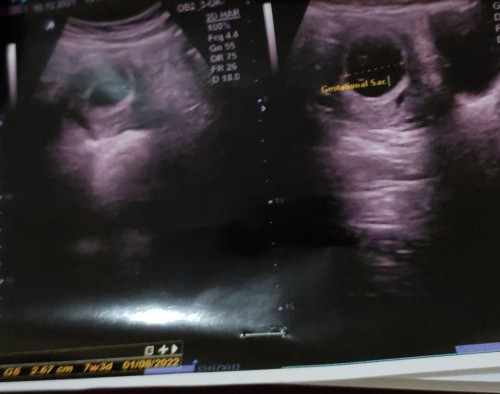

Bund aku mau tanya nih kebetulan ini anak pertama jdi aku krg pemahaman. Jdi aku hpht hrusnya 9minggu dan pas di usg ternyta bru 7w3d dan itu pun janin nya belum terlihat. Terus aku di suruh balik lagi 2 minggu lagi dan di kasih obat penguat kandungan sama dokter. Kira kira normal gg ya bund di umur sgtu janin nya belum terlihat. Bantu jwb bunda bunda 🙏#seriusnanya #bantusharing